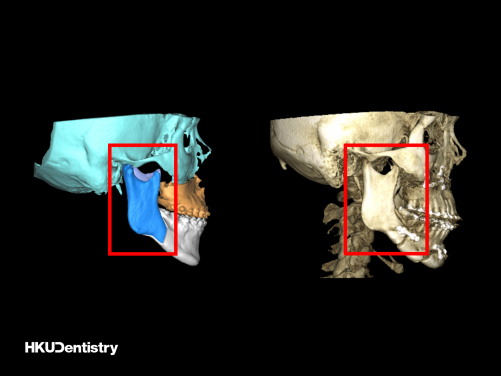

Intraoral vertical ramus osteotomy (IVRO): (Left) The pre-operative virtual surgical planning (red frame); (Right) The post-operative CT scan (red frame).

Mandibular prognathism is a common facial deformity in Hong Kong and Southern China when compared to Western countries. The correction of mandibular prognathism requires orthognathic surgery, which involves creating a split in the jawbone(s) and fix in a planned position. Intraoral vertical ramus osteotomy (IVRO) and sagittal split ramus osteotomy (SSRO) are the two common surgical techniques of the lower jaw to setback the elongated lower jaw. IVRO is an older technique that requires intermaxillary fixation to achieve bone fixation, i.e. locking the upper and lower jaws with wire, for 6 weeks. During this period, the patient can only take fluid diets. SSRO, in contrast, allows internal fixation using titanium plates and screws, which enables immediate jaw function after the surgery. Both techniques are commonly used in Hong Kong and Eastern Asia in treating patients with mandibular prognathism.